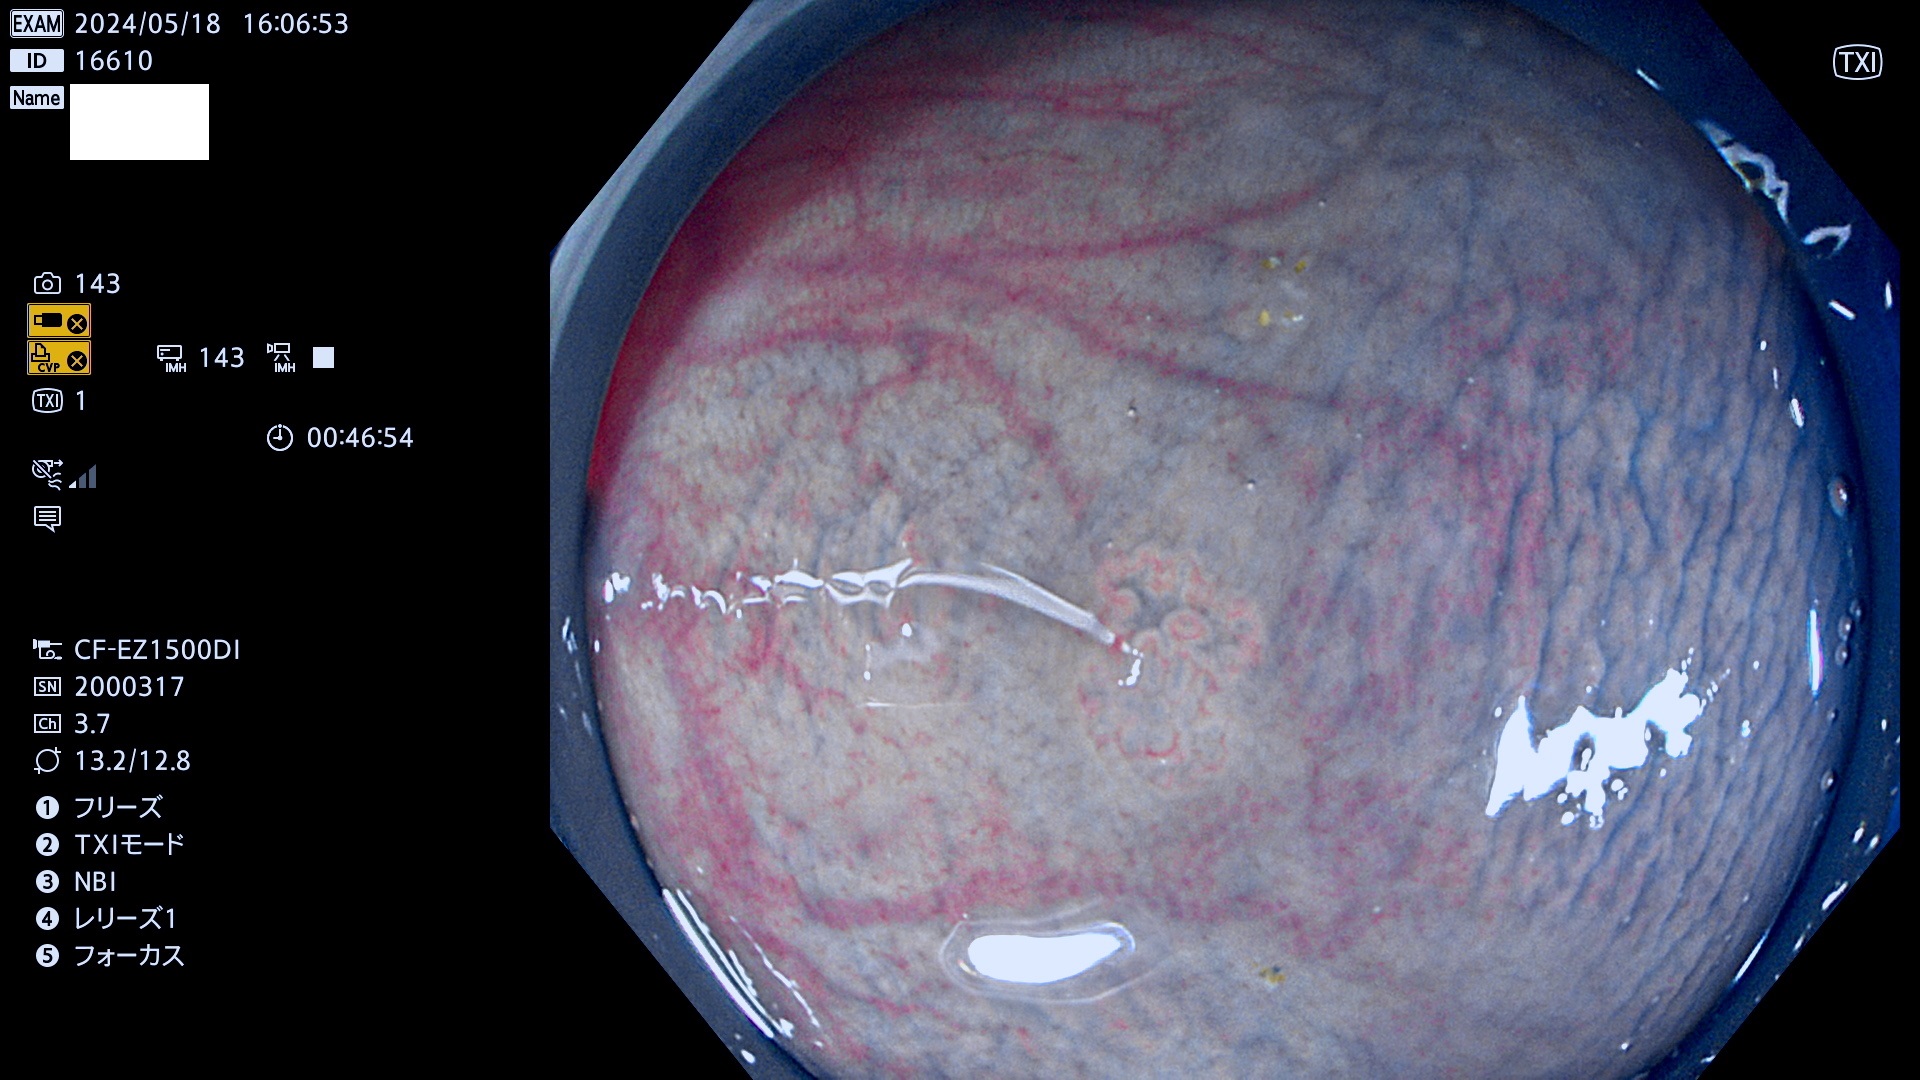

表面型腺腫(Flat Adenoma)の中で、完全に平坦な物をUb、陥凹している物をUcと呼びます。平坦隆起型(Ua)よりも、発見が難しく危険な病変です。

毎週の検査(木・金・土・日)に発見されたUb、Uc型・腺腫を、その週の日曜の夜にUPし1週間、提示します。

抽出の対象期間 2024年5月16日〜5月19の4日間(40件の検査)10件 (10/40=25%)